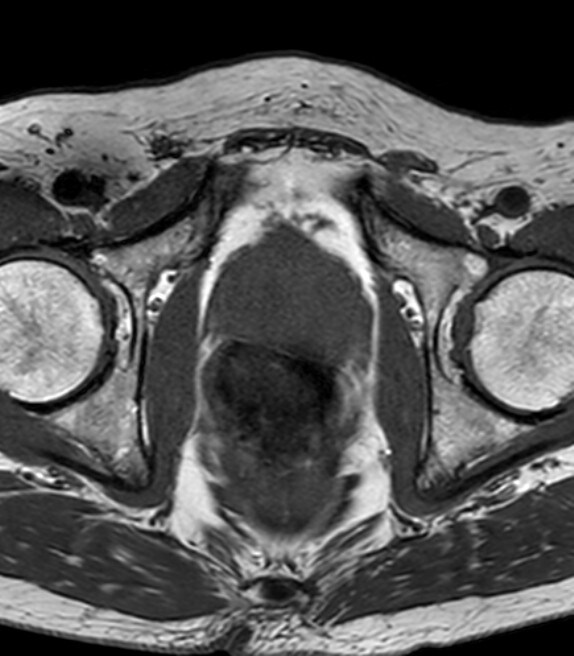

本症例ではPSA高値を契機に前立腺MRI検査を施行した。便秘症があるため、直腸は拡張し、内部にガスを含む便塊を認める。鎮痙薬は、既往症のため、使用せず、検査前の排便も不可能であったために、画質劣化が避けられない。腸管ガスによるひずみの影響で、全ての撮像シーケンスで、前立腺の後方の辺縁は不鮮明で、内部の信号が不均一となる。特に空気や蠕動の影響を受けやすい、拡散強調画像での画質劣化が著しい。

近年、前立腺癌のMRI診断のばらつきを減らし、撮影・読影方法を標準化するために、Prostate Imaging and Reporting and Data System(PI-RADS)が広まっている。これは、治療介入が必要な前立腺癌の検出を目的としている。現在のPI-RADS v2.1では、T2強調画像、拡散強調画像、ダイナミック造影画像を個別に評価し、各画像でスコアを付け、定められたルールに基づいて統合し、臨床的に意義のある癌の疑い度合いを5段階で分類する。PI-RADS v2.1では、質の高いT2強調画像と拡散強調画像があれば、必ずしも造影検査は必要ない。

拡散強調画像(DWI)では、腸管ガスによるひずみの影響を減らすため、echo planar imaging(EPI)を用いたDWIよりTurbo spin echo(TSE)を用いたDWIを使用する。high b valueの画像は、computed DWIで作成することで、実際の撮像よりもノイズを低減できる場合がある。また、ダイナミック造影MRIを追加すると、短時間撮影のため前立腺の輪郭も明瞭で、癌部と非癌部のコントラストがつき、病変の検出に役立つ場合がある。